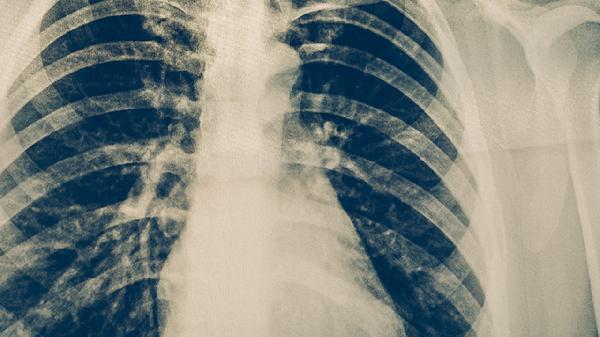

胸部X線或CT檢查能發(fā)現(xiàn)肺結(jié)核特征性病變,如肺上葉尖后段浸潤影、空洞形成等。影像學(xué)表現(xiàn)需與肺炎、肺癌等疾病鑒別,活動性病變多呈現(xiàn)邊緣模糊的斑片狀陰影。該方法無法區(qū)分活動性與陳舊性病灶,需結(jié)合臨床癥狀和其他檢測綜合判斷。兒童肺結(jié)核患者可能僅表現(xiàn)為肺門淋巴結(jié)腫大。